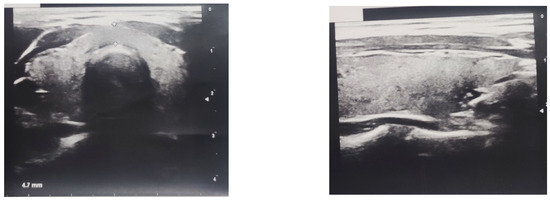

The ultrasound scan showed a hypoechogenic, non-homogeneous-structured, and normal-sized thyroid gland (Figure 2), as well as normal structures and sizes of the liver and the spleen.

Figure 2. Ultrasound scan of patient’s hypoechogenic, non-homogeneous-structured, normal-sized thyroid gland.